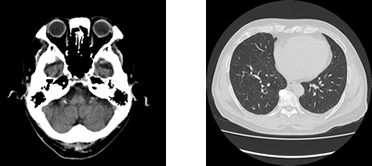

CT検査

CTとは、ComputedTomography(コンピューター断層撮影)の略語です。X線を利用して、体内の情報を集め計算により人体の横断像 (輪切り)を撮影することが出来ます。検査時間は、検査の内容や部位によって異なりますが約5~20分程度の短時間ですみます。また、造影剤を使用することにより、あらゆる血管(脳・胸部・腹部・上下肢血管)や腫瘍などの撮影が可能となります。

さらに、CTで収集したデータを用い画像処理ワークステーションを使用して様々な方向の断層像や、骨や血管などの3D画像を作成することも可能です。(下記の心臓CT検査やCTコロノグラフィー検査もワークステーション処理によるものです)

2019年4月より当院は最新のCT装置を導入し、従来の装置と合せ2台運用とすることで救急医療にも更に迅速に・いつでも対応できるよう体制を整えています。

キャノンメディカルシステムズ(株)(旧:東芝メディカル)の80列マルチスライスCTスキャナでAquilion Prime SPという装置です。

キャノンメディカルシステムズ(株)(旧:東芝メディカル)の80列マルチスライスCTスキャナでAquilion Prime SPという装置です。

80列マルチスライスCTの特徴

- 1.

- これまでの装置と比べより高速に撮影出来るようになったので胸部や腹部の検査などで息を止める時間が短くなります。(胸部から全腹部で5~10秒程度、胸部だけなら2、3秒でも撮影可能です。)心臓の特殊な検査もわずか3心拍でも可能となっています。

- 2.

- X線の被ばく低減と画質向上の新技術として逐次近似法を用いたAIDR 3D Enhancedを搭載しており、被ばく量を減少しつつ(以前の装置に比べ30%以上の低減率)より高精度の画像を撮影することが可能となりました。

- 3.

- 検査台も広く、CTスキャナの口径も直径78cmと大きくなっており以前の装置よりも圧迫感が和らいでいます。検査台は33cmまで下がるので、年配の方にもやさしい仕様となっております。

- 4.

- 今回、3Dワークステーションも最新のZiostation2 PLUS ClassicHに更新いたしました。

これにより、以前よりも処理・解析時間が短縮され、画質も向上しています。 - 5.

- その他にも様々な新技術が搭載されており、短時間で高画質を実現しています。